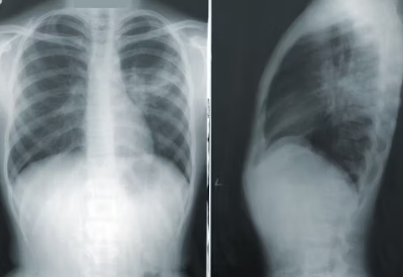

- 폐렴: 숨 막히는 고통의 시작

- 왜 위험한가? 혈당이 높으면 폐포를 보호하는 기능이 약해져 폐렴균이 쉽게 침투할 수 있습니다. 특히 당뇨병 환자는 폐렴구균에 대한 면역 기능이 떨어져 있어 폐렴 발생 위험이 3배 이상 높고, 폐혈증 등 치명적인 합병증으로 이어질 가능성이 큽니다.

- 주의할 점: 단순 감기 증상으로 넘기지 말고, 고열, 기침, 가래, 호흡곤란 등의 증상이 나타나면 즉시 병원을 방문해야 합니다.